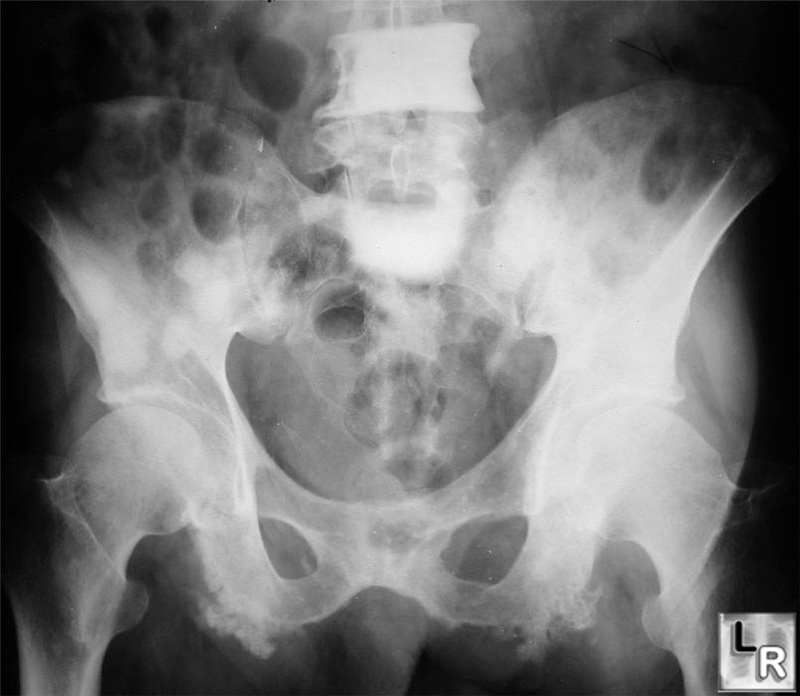

Gãy xương có thể xảy ra do té ngã hoặc chấn thương, nhưng xương yếu cũng có thể bị gãy khi hoạt động bình thường. Gãy xương thường xảy ra nhất ở các xương dài ở cánh tay, chân và cột sống. Nếu bạn bị đau đột ngột ở giữa lưng, bạn có thể bị gãy xương ở cột sống. Nếu chụp X-quang cho thấy xương ở cánh tay hoặc chân của bạn có thể bị gãy, bác sĩ có thể đề nghị phẫu thuật để chèn một thanh kim loại vào xương yếu. Khi xương bị gãy, phẫu thuật thường được thực hiện để đặt khung kim loại lên xương gãy.